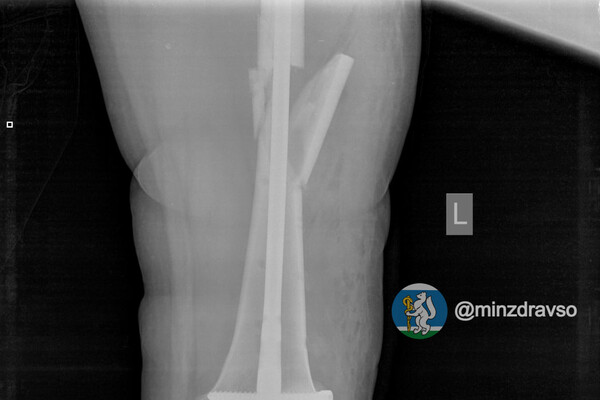

В Екатеринбурге 41-летняя беременная женщина упала с высоты десяти метров. В результате у нее диагностировали ушиб головы и сложный оскольчатый перелом левой бедренной кости, угрозы прерывания беременности медики не выявили.

Пациентке провели первую операцию в шоковой операционной приемного отделения. Через неделю, когда ее состояние стабилизировалось, женщине выполнили вторую операцию по замене аппаратов внешней фиксации на внутренний фиксатор. Для дальнейшего ведения беременности ее перевели в другую больницу.